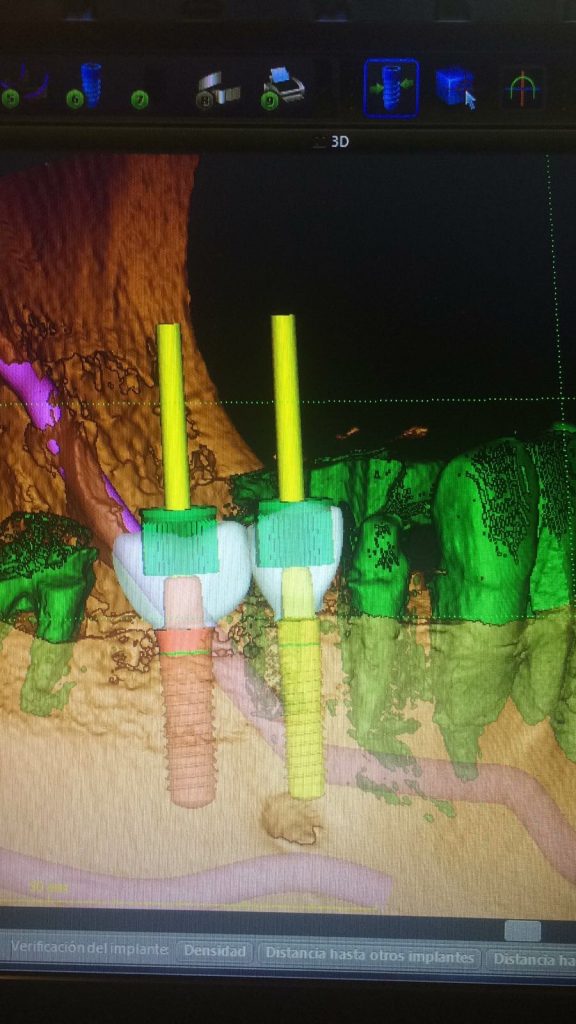

Autores: PRÓLOGO Asimismo, desde el punto de vista pedagógico, el profesional nobel en la materia tiene a su alcance la posibilidad de corregir cualquier posición implantaría en el ordenador, planear los provisionales y plasmarlos en la bio réplica antes de tocar al paciente a operar. Todos estos razonamientos nos llevan a presentar un caso de condiciones muy favorables para poner en práctica estos métodos como primer acercamiento a una Odontología Digital de alta calidad, con medios informáticos, que ya están presentes en la profesión de hoy en día, y será la protagonista única del futuro. Por otro lado, después de numerosos estudios que nos llevan a plantear el “gap” entre implante y pilar(abuttment), como principal responsable de la periimplantitis dado que la microbiota presente en el mismo es imposible de limpiar y en su presencia la cortical ósea reacciona reabsorbiéndose, nos ha llevado a utilizar implantes monobloc ya que los ejes implantarios y protéticos coincidían, y nos permitían su uso. Además, el circonio, ha mostrado a la luz de estudios muy recientes, una preservación y adhesión de los tejidos blandos superiores al titanio, tanto en su tratamiento de superficie de la rosca como a nivel gingival. DESARROLLO Paciente varón de 68 años, con antecedentes de radio/quimioterapia cinco años antes, con Rehabilitación Oral de los cuatro cuadrantes, con una Oclusión Mutuamente Compartida conservada, (REF.8) la que fracasa en el cuadrante 4, 19 años después. El mismo presentaba un puente de porcelana sobre circonio con pilares en 44 y 47, reemplazando el edentulismo de 45 y 46. Se produce la fractura del PM del 44, y ante una endodoncia antigua y corta, se decide implantar las zonas edéntulas, conservando temporariamente los pilares, hasta producida la oseointegración, para entonces también exodonciar el 44. DIAGNÓSTICO Tomamos impresiones del maxilar antagonista, Arco Facial Estático y realizamos montaje del mismo mediante la sistemática ARTEX. Producimos la relajación del músculo Pterigoideo Externo, para obtener la ORC (Oclusión en Relación Céntrica) mediante el método de Laminillas de Long, basado en el concepto de INERVACIÓN RECÍPROCA. Esto nos permitirá montar el maxilar inferior, tanto en su forma de: La primera para practicar la cirugía guiada y comprobar su eficacia, y el modelo de yeso para ser escaneado y confeccionar la GUÍA QUIRÚRGICA. La Biorréplica la obtenemos transformando los archivos DICOM que nos da el CBCT en archivos STL, y a partir de ellos, mediante una tecnología de PROTOTIPADO RÁPIDO, la obtención de un objeto físico en 3D a través de la aglutinación selectiva de una sucesión de capas de polvo. Procedemos a montar la biorrèplica y el modelo de yeso del caso. Podemos verificar la exactitud de las medidas del hueso residual en la bio réplica y compararlas con el scanner. Arrojando un resultado de 8,5 mm de cortical externa a cortical externa. Pudiendo también medir la distancia hasta el dentario. y comparar gracias a la ventana lateral de la biorréplica Dándonos 22mm de distancia. Con lo cual deducimos que implantes de 4,1mm por 12 mm serán perfectamente rodeados de hueso. Medimos también la distancia desde oclusal del antagonista, hasta el hueso desnudo. Lo mismo que, mediante la utilización de la guía radiológica, con un material radiolúcido colocado en gingival de la misma, podemos medir la altura de la encía. Con lo cual podemos calcular la altura del pilar. Es entonces cuando con el programa COC Diagnostix se realiza la programación final: Obteniendo no solo la ubicación, largo, ancho y ángulo de los implantes sino también los provisionales mediante CAD CAM. Ya entonces podemos hacer la práctica quirúrgica en la bio réplica, mediante la guía quirúrgica, instalando los implantes de prueba que no serán los de circonio, ya que la casa no cuenta con ellos, pero si otros de las mismas dimensiones. TRATAMIENTO Entramos ya en la cirugía propiamente dicha. Antisepsia de la zona a operar y zonas anexas. Comprobación del perfecto ajuste e inmovilidad de la G.Q. en boca durante la cirugía. Marcado de la encía y perforación de la cortical. Visión a través de la Guía de la mínima intervención anterior. Comprobación sin Guía. Incisión mínima mesio distal, para apartar y conservar encía queratinizada. Secuencia de drills, perforando a profundidad requerida Observación del Mínimo Trauma Implantes Strauman de Zirconio Monoblock en blíster y montádo en contrángulo reductor. Instalación controlando torque con contrángulo reductor. Comprobación clínica. Comprobación Radiográfica y con Guía. Toma de impresiones, y armado de modelos con técnicas de pasividad protética. Montaje. Resultado de las provisionales ejecutadas por CAD CAM Al no estar conformes con el resultado decidimos desechar dichas provisorias y optar por repetirlas. Nuevas provisorias realizadas mediante encerado convencional. Estado de los tejidos blandos. Provisorias en boca. Oclusión de Estímulo Inmediato. Ref.10: Carga inmediata .Alberto y Diego Bechelli. Comprobación mediante CBCT post operatorio Componentes del equipo (En la próxima presentación, mostraremos las coronas definitivas de porcelana sobre circonio, y la desoclusión provocada por una OCLUSIÓN MUTUAMENTE COMPARTIDA, sobre estos implantes y otros seis mas) REFERENCIAS

FIG: 21-22-23-24-25-26

Fig. 21

Fig. 22

Fig. 23

Fig. 24

Fig. 25

Fig. 26

Mas adelante, y por cuestiones de conveniencia protética, el implante instalado del premolar será de 3,3 mm.